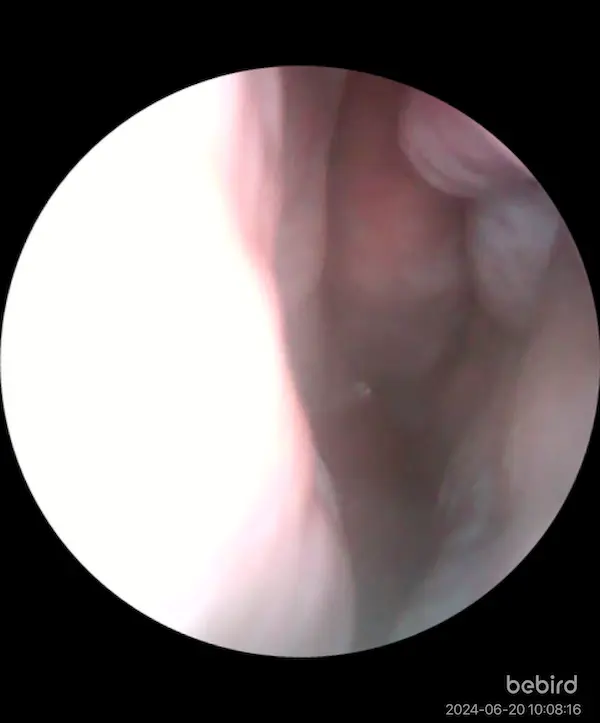

エンプティノーズの手術から8ヶ月経ったが、過去イチで快適だ。 一切のドライ感もないし、1日中完全に通っている。 下鼻甲介自体ないので、アレルギー性の鼻水も出ない。 鼻の学歴はかなり高い。みなさんはどうだろうか。

エンプティノーズ手術前は、もともと夏にあって暑くなってくるとなぜか詰まる という現状があり、最近2度の手術はどちらも、 夏になって鼻詰まりが強くなったことで受診した結果である。 先生に、夏になると詰まるということを言うと不思議がってた。 サウナに入ると鼻が詰まって死ぬほど苦痛だったが、これも消失した。

これはおれの勘だが、 エンプティノーズの場合、鼻腔が広すぎるので 特に夏で外気が暑くなると鼻腔の中のTRPM8が全く活性化されない。 そのため、鼻呼吸の感覚がエンプティになる。 それが手術によって鼻腔を狭めたことによってジェット気流による冷却が発生し、改善したという理屈ではないだろうか。 そして今、鼻腔の冷却具合が夏でも十分になると、 今度は冬に比べて空気が湿っていてドライ感がなくなり、快適になる。 これが、夏になってきて鼻が快適になってきた理由だと思う。 鼻科学は理詰めだ。